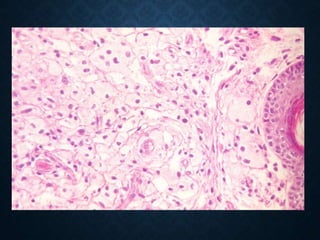

Foam cells (histiocytes)

(HE) x 200